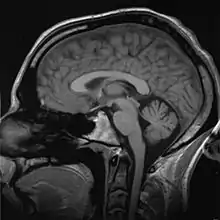

Biomedical engineering has recently emerged as its own study, as compared to many other engineering fields. Such an evolution is common as a new field transition from being an interdisciplinary specialization among already-established fields to being considered a field in itself. Much of the work in biomedical engineering consists of research and development, spanning a broad array of subfields (see below). Prominent biomedical engineering applications include the development of biocompatible prostheses, various diagnostic and therapeutic medical devices ranging from clinical equipment to micro-implants, common imaging equipment such as MRIs and EKG/ECGs, regenerative tissue growth, pharmaceutical drugs and therapeutic biologicals.

Imaging technologies are often essential to medical diagnosis, and are typically the most complex equipment found in a hospital including: fluoroscopy, magnetic resonance imaging (MRI), nuclear medicine, positron emission tomography (PET), PET-CT scans, projection radiography such as X-rays and CT scans, tomography, ultrasound, optical microscopy, and electron microscopy.